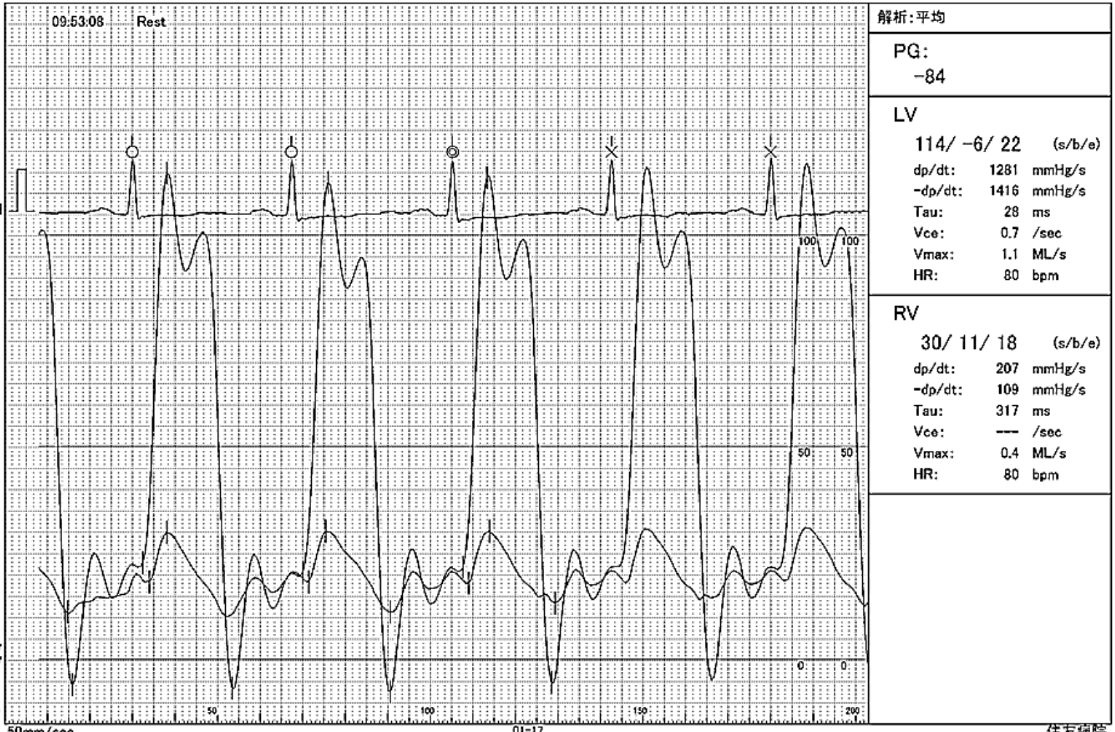

Right heart catheterization demonstrated hemodynamic findings: The LVEDP–RVEDP gradient was 4 mmHg (< 5 mmHg), and the RA pressure waveform demonstrated a deep y descent (Fig 5). Both right and left ventricular pressure tracings showed a characteristic dip-and-plateau pattern. No significant respiratory discordance was observed between LVSP and RVSP (Fig 6).